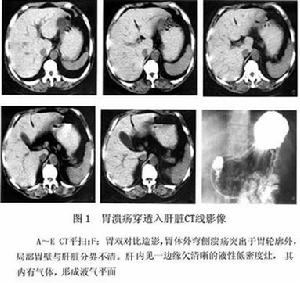

(3)CT檢查:胰腺內出現團塊、假性囊腫,或胰管內出現氣體,是胰腺被穿破的徵象。胃潰瘍穿透入肝臟,表現為胃壁漿膜面輪廓不清,與胃壁緊密相連的肝臟邊緣處出現液性低密度影其內可有氣體,並可形成小的氣液平面低密度邊緣模糊(圖1)。